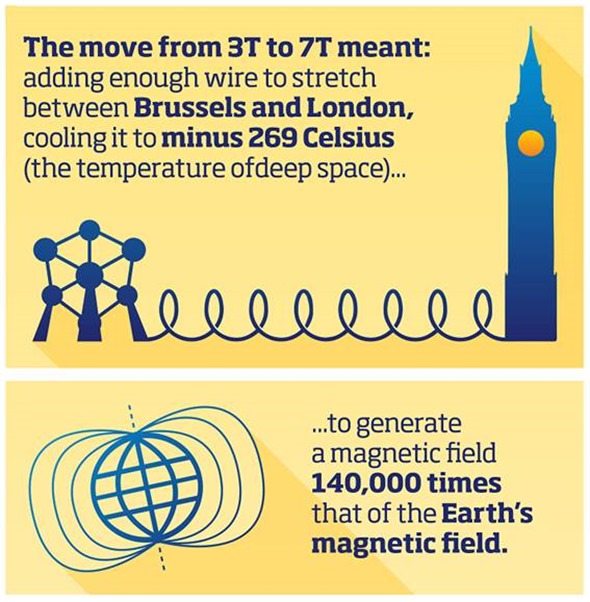

Achieving such a jump in magnetic field was a huge engineering challenge. A MRI magnet is composed of a number of coils of thin wires carrying a very high current. The move from 3T to 7T required the addition of enough wire to stretch between London and Brussels.

These coils then need to be cooled to 4.2 Kelvin (minus 269 Celsius) – the temperature of deep space – to enable the wire to become superconducting and carry enough current to generate a magnetic field 140,000 times that of the Earth’s magnetic field.